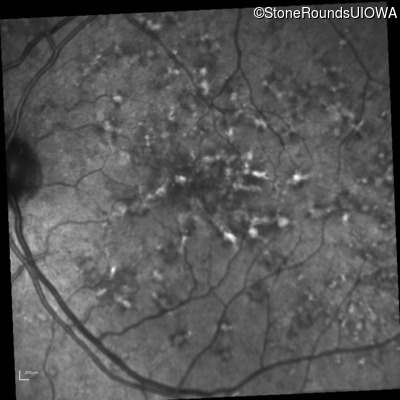

Fluorescein Angiography - Right - 20/40 +2 sc

Exemplar